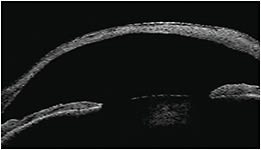

Anterior segment OCT (AS-OCT) plays a significant role in angle-closure glaucoma management as it provides an effective method of viewing the anterior chamber angle.

While diagrams are great, imaging the patient’s anterior chamber angle and showing them your concern of potential angle closure is made much simpler by AS-OCT images. Utilizing AS-OCT images bolsters the patient’s understanding and acceptance of peripheral iridectomy.

AS-OCT is not required to diagnose the vast majority of narrow angle glaucoma cases. However, there’s nothing more reassuring to confirm your diagnosis than qualitative and quantitative assessment of the anterior segment with AS-OCT.

Determining the anterior chamber angle status with gonioscopy alone leaves open a level of interpretation. If I am uncertain about proceeding with glaucoma surgery after performing gonioscopy (especially after inadequate visualization, analyzing AS-OCT images helps me to make a final decision. OM